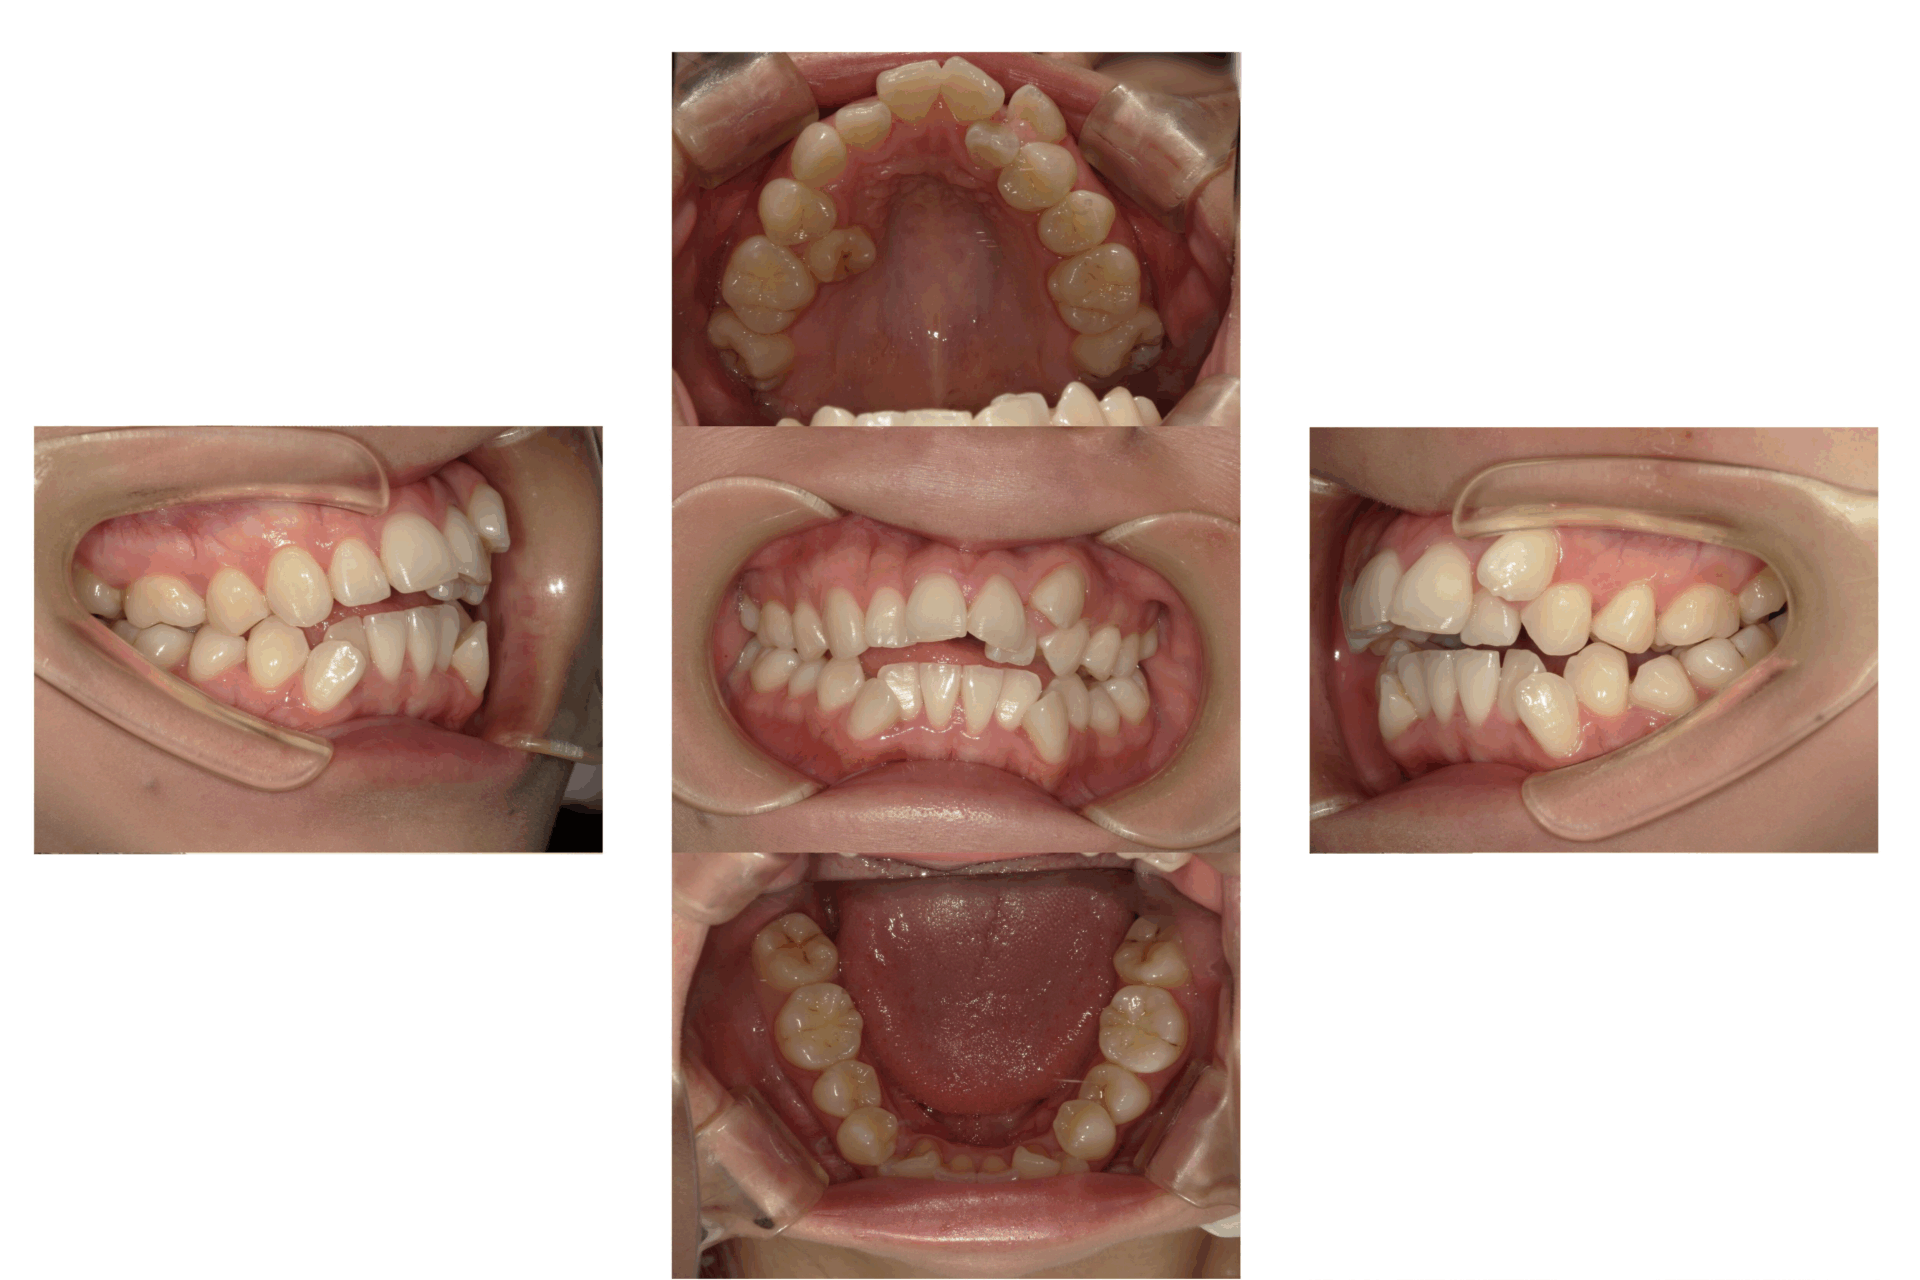

10代、女性、ワイヤー

| 施術内容 | 主訴:上下前歯でこぼこ。なるべく抜きたくない。 詳細:ワイヤー矯正での歯並び改善 詳細:ワイヤー矯正での歯並び改善 歯肉炎リスクあるため、今後は後戻りのチェックとともに歯肉炎管理もしていきます。 |

|---|---|

| 治療期間 | 12ヶ月(2/6現在 治療終了) |

| リスク・副作用 | ■リスク・副作用 ・治療の初期段階では、痛みや不快感が生じやすくなりますが、一週間前後で慣れます。 ・歯の動き方には個人差があるため、予想された治療期間より延長する場合があります。 |

| 費用 | ワイヤー矯正 60万円(税込660,000円) |